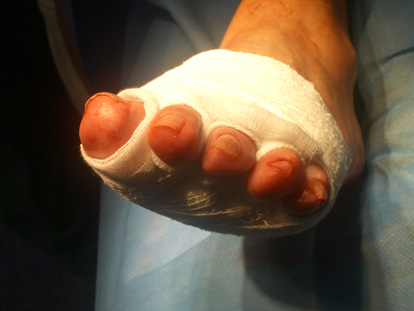

Vendatge post operatori